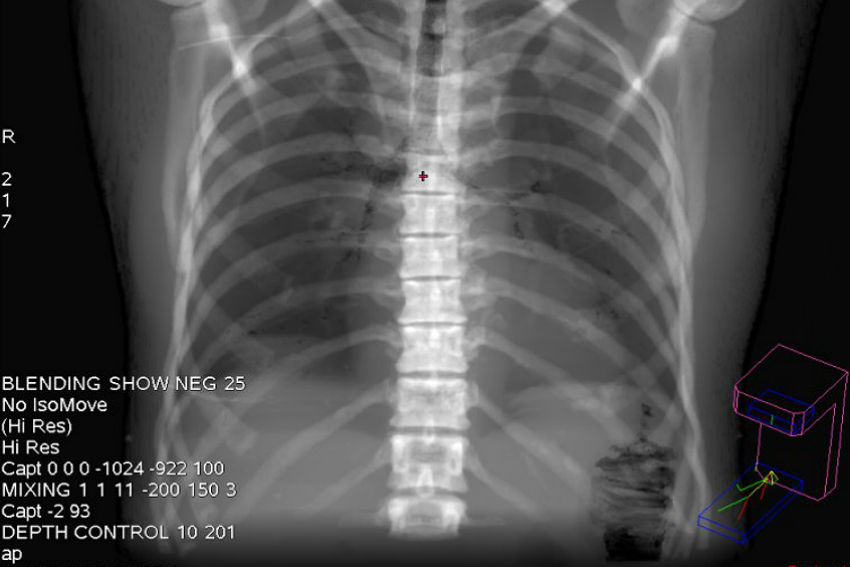

Eine schonende Lösung für viele Patienten ist die bild- oder CT-gesteuerte Therapie bei Schmerzen der Wirbelsäule. Durch krankhafte Veränderungen von Knochen und Bandscheiben bedingte akute und chronische Beschwerden können so minimalinvasiv behandelt werden, wenn durch konservative Maßnahmen keine Besserungswerte mehr erzielt werden.

Bei dieser Art der Therapie werden vom Neuroradiologen unter CT-Kontrolle schonende Infiltrationsverfahren eingesetzt. Diese erlauben mit hoher Präzision und Sicherheit und unter der Wirkung schmerz- und entzündungshemmender Medikamente punktgenau die Schmerzleitung zu unterbrechen, häufig sogar die Ursache zu behandeln und den Heilungsvorgang zu beschleunigen. Auf eine für die Patienten risikobelastende Vollnarkose und Operation kann so verzichtet werden.

Die Vorteile der CT-gesteuerten Wirbelsäulenschmerztherapie liegen auf der Hand: Bei der CT-Steuerung werden Nadel und Medikamente millimetergenau positioniert. Entsprechend ist die Wirkstoffkonzentration am Schädigungsort der Wirbelsäule extrem hoch und es besteht eine hohe Sicherheit zur Vermeidung von Nerven- und Gefäßverletzungen. Zudem ist diese Therapie weitgehend schmerzfrei und hat eine hohe Erfolgsquote. Bei der ambulanten, minimalinvasiven Durchführung besteht auch kein Risiko einer Narbenbildung, wie z. B. nach einer Bandscheiben-OP.